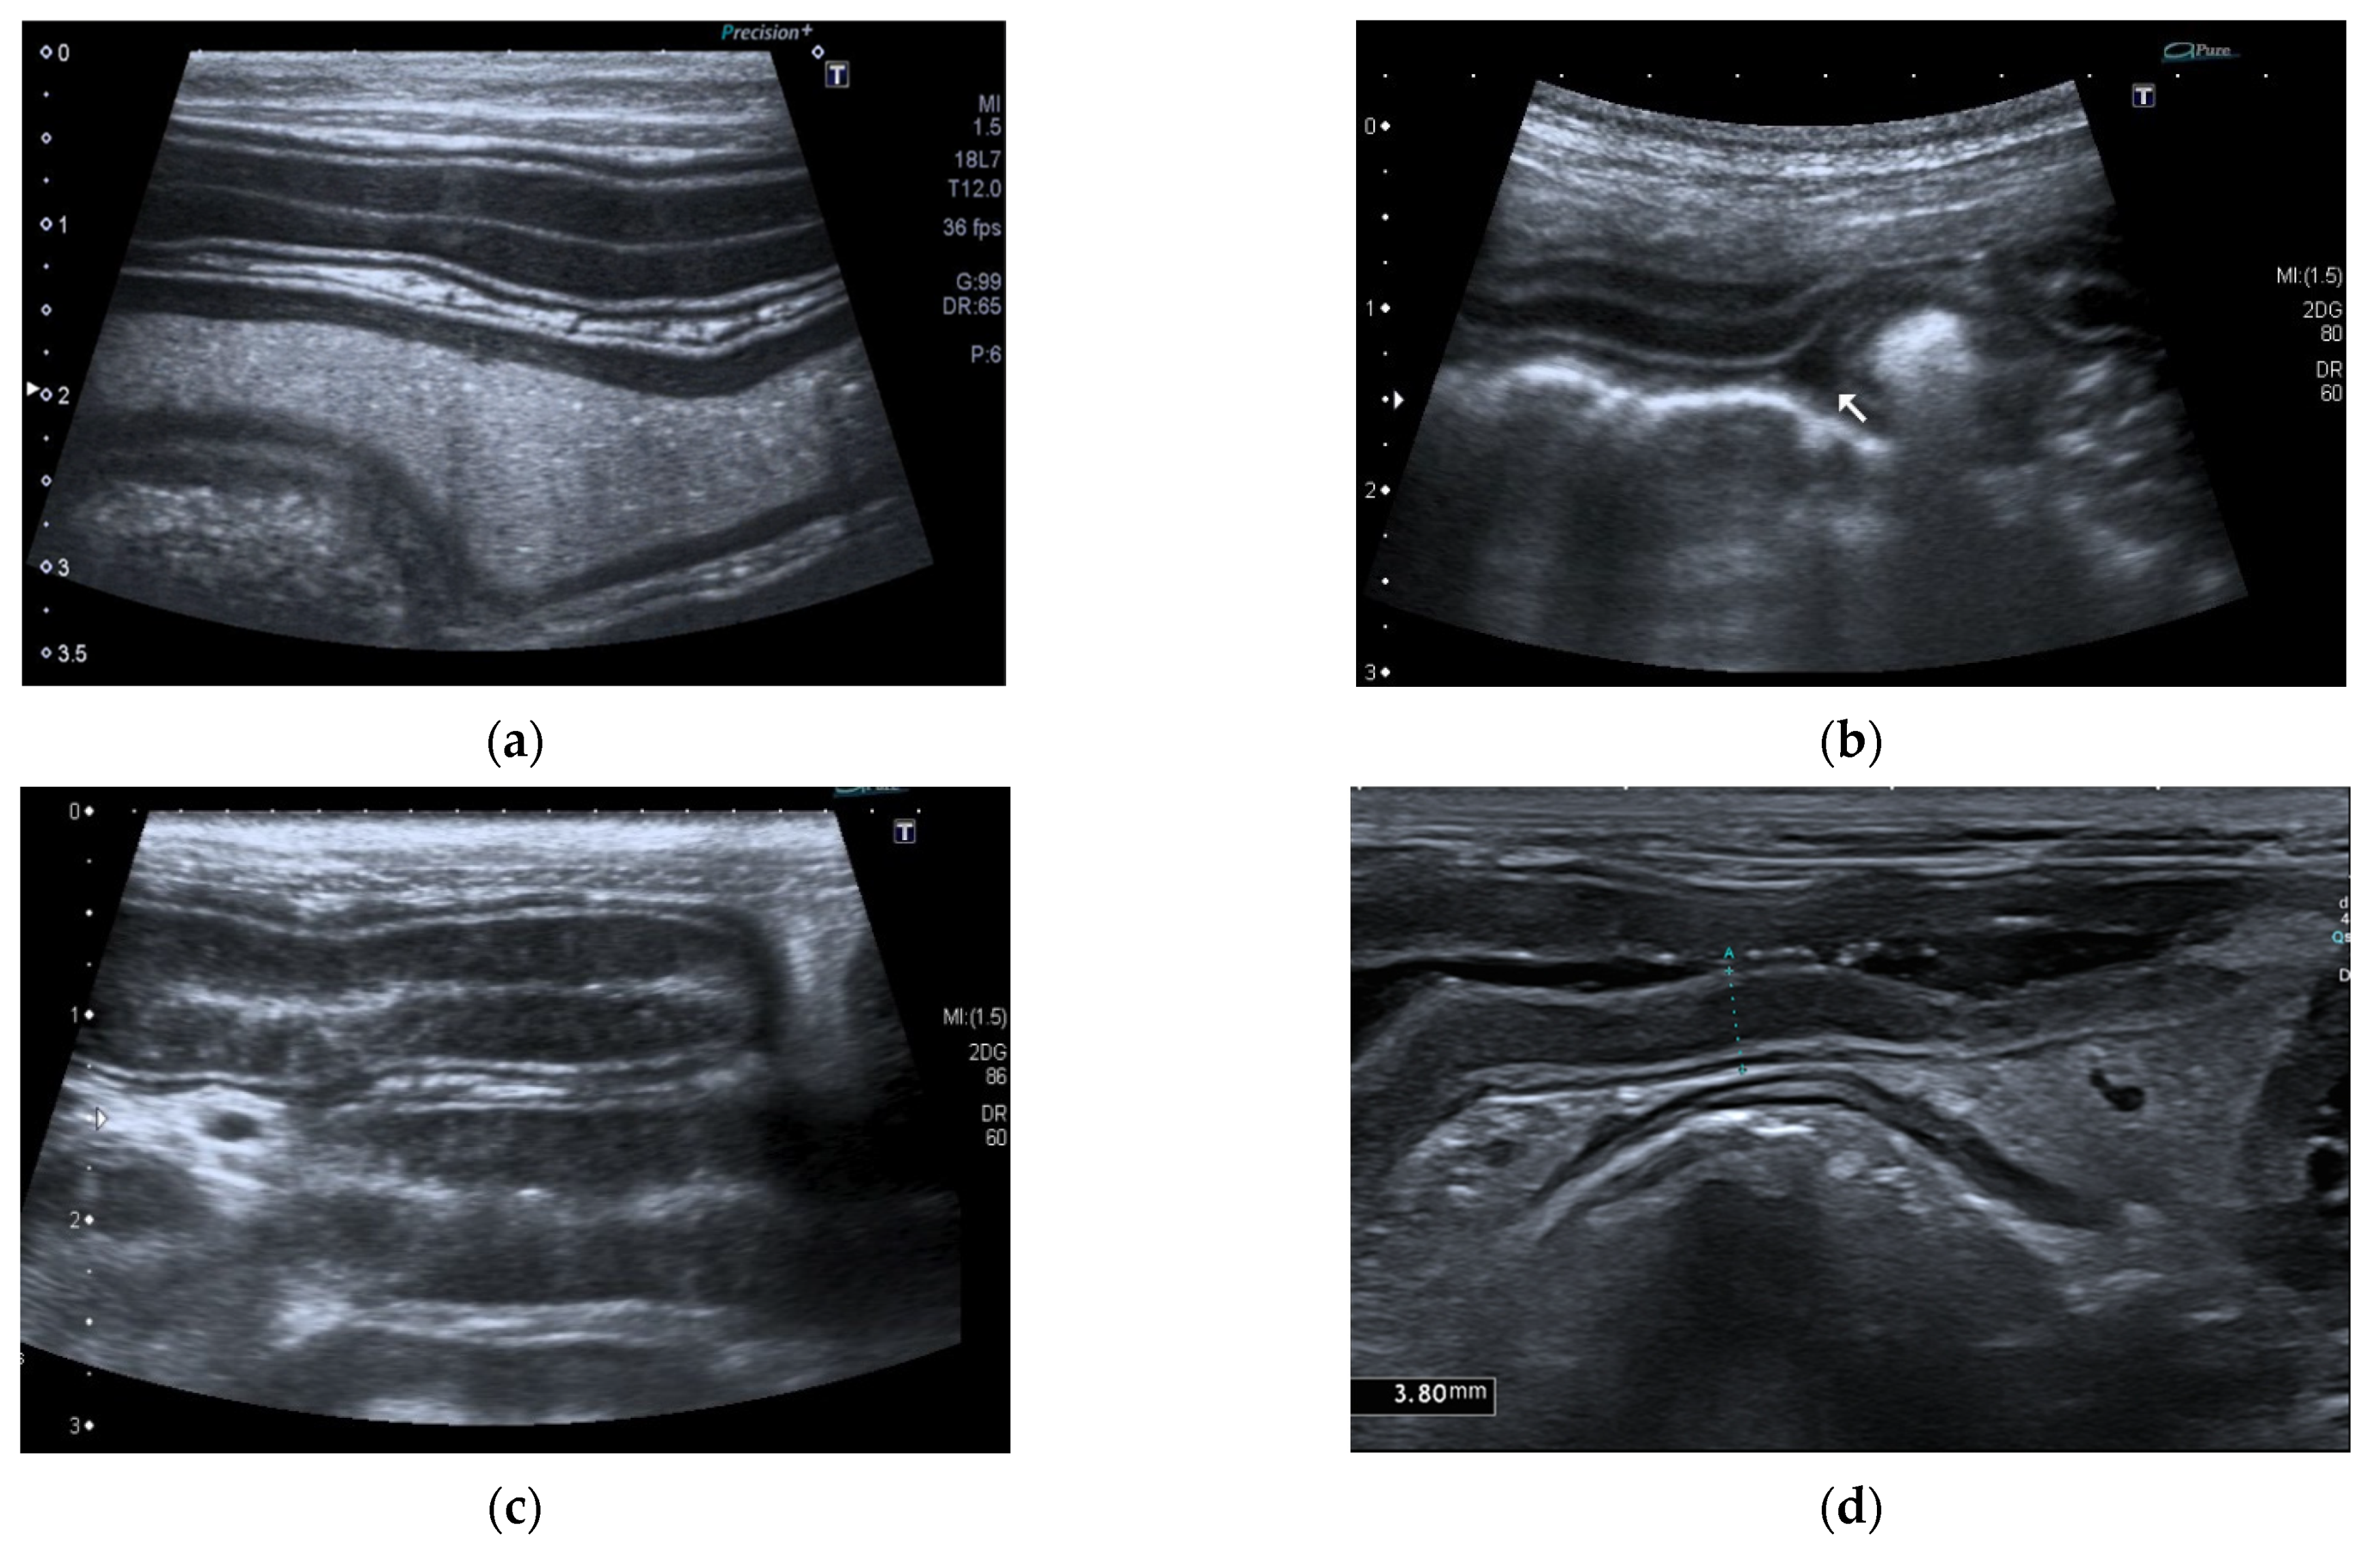

Ultrasonographic intestinal abnormal findings were identified in 85% (29/34) of dogs, and the ultrasonographic findings are summarized in Table 4 (Figure 4).

Figure 4.

Ultrasonographic intestinal abnormal findings. (a) Jejunal dilatation with fluid content; (b) Mild abdominal effusion; (c) Jejunal segment with hyperechoic striation within the mucosa; (d) Jejunal segment with hypoechoic/nearly anechoic mucosa and fluid content.